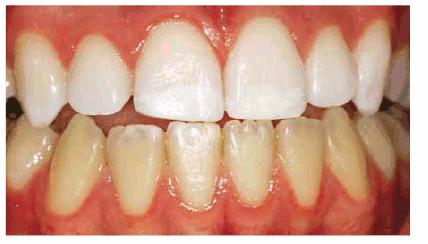

chromogenic foods, and beverages (Figures 16-16A 16-16B 16-17A, and 16-17B). Although these types of stains

Figure 16-16A: Some teeth darken over time from chromagenic foods. Some patients' teeth are just naturally yellow.

Figure 16-16B: Whitening of the maxillary teeth using 10% carbamide peroxide in a custom tray results in a more pleasing smile. This patient is now interested in closing the spaces.

Figure 16-17A: Some teeth darken through natural aging.

Figure 16-17B: Whitening of the maxillary teeth using 10% carbamide peroxide in a custom tray produces a normal progression of color from gingival to incisal edge but offers a more pleasing, younger look to the patient.